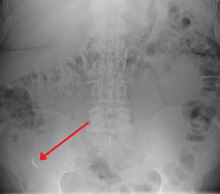

| A fecolith marked by the arrow which has resulted in acute appendicitis. | |

Appendicolith as seen on plain X ray